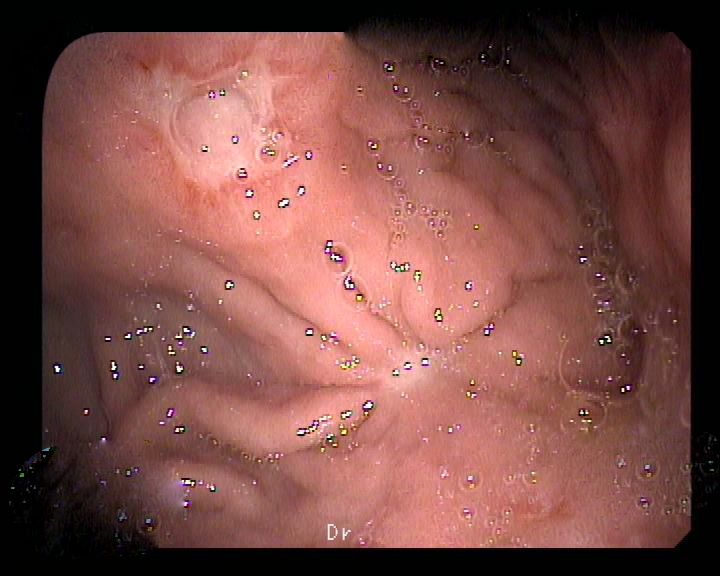

Paciente mujer de 72 años de edad con antecedentes de cardiopatía isquémica (IAM anteroseptal),TEP leve (tratamiento con acenocumarol) y trastorno depresivo. Consulta en enero del presente año por clínica dispéptica inespecífica sin síntomas de alarma. Anlíticamente no se encontraron alteraciones de interés. Se realizó una gastroscopia que observó cierta dificultad en la distensión de la cámara gástrica a la insuflación con biopsias de cuerpo y antro gástrico para determinación de H. Pylori (ureasa rápida), que resultó positivo. Se hizo tratamiento erradicador para H. Pylori (pauta con amoxicilina y claritromicina durante 7 días) que resultó eficaz. En el TAC abdominal se apreciaba engrosamiento parietal circunferencial de la porción distal del antro y píloro con mala definición de la transición con el tejido graso adyacente en el borde mesentérico que no permitía descartar afectación mas allá de la serosa. Ante estos hallazgos se realizó una USE radial: se observa en zona de transición de cuerpo-antro sobre todo hacia curvadura mayor, unos pliegues engrosados con poca distensibilidad a la insuflación y friable al roce con erosiones fibrinadas. Estenosa levemente la luz. Se observa un engrosamiento de la segunda y tercera capa que rompe en algunas zonas primera capa. La cuarta capa y serosa parecen respetadas. No se observa infiltración de parénquima hepatico ni cuerpo-cola pancreática. Sugiere proceso neoformativo (linfoma?). Por este motivo se solicitó una macrobiopsia gástrica que resultó inconcluyente (metaplasia enteroide).

La presencia de unos pliegues gástricos engrosados en una gastroscopia y/o pruebas de imagen (TAC, ecografía abdominal y USE) es un verdadero reto diagnóstico ya que en algunos casos se trata de una patología benigna sin trascendencia clínica (gastritis folicular por H. Pylori) hasta cuadros de mayor entidad como el síndrome de Zollinger-Ellison, la gastropatía hipertŕofica de Menètrier, el linfoma MALT gástrico y el adenocarcinoma gástrico en su presentación como linitis plástica. Hay que tener mucho cuidado en estos casos porque cuando se trata de una neoplasia, el crecimiento celular se hace a expensas de la mucosa profunda y submucosa, y aunque puede haber ulceraciones, muchas veces las biopsias con fórceps son repetidamente negativas. En estos casos, una buena macrobiopsia con asa de polipectomía nos puede ayudar al diagnóstico definitivo.